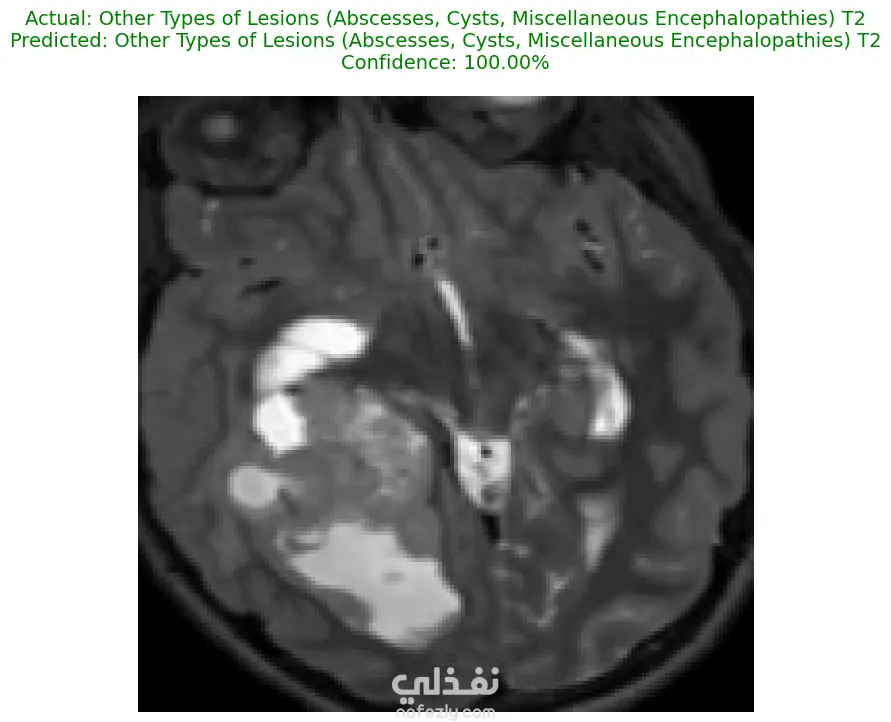

الوصف: قمت بتطوير نموذج تعلم عميق (CNN) قادر على التمييز بين 27 فئة مختلفة من الأورام والحالات الطبيعية بدقة تصل إلى 93%. شمل المشروع مراحل معالجة البيانات الضخمة، تنظيفها وموازنتها، وتصميم معمارية مخصصة لضمان الكفاءة العالية وتقليل استهلاك الذاكرة. المميزات التقنية: دقة استثنائية: حقق النموذج دقة تصل إلى 93% على بيانات التحقق (Validation Accuracy). معالجة البيانات الضخمة: تم العمل على قاعدة بيانات ضخمة، مع تطبيق استراتيجيات موازنة البيانات (Data Balancing) لضمان عدم انحياز الموديل. معمارية مخصصة: تم تصميم شبكة CNN تدعم تقنيات Batch Normalization لتسريع التعلم و Global Average Pooling لتقليل استهلاك الذاكرة وضمان استقرار النموذج. معالجة الصور: استخدام تقنيات OpenCV لقص الصور (Cropping) وإزالة الهوامش غير الضرورية لتركيز الموديل على منطقة الورم فقط. الأدوات والتقنيات المستخدمة: لغة البرمجة: Python. المكتبات الأساسية: TensorFlow / Keras. معالجة الصور: OpenCV & PIL. تحليل النتائج: Scikit-learn (Confusion Matrix & Classification Report). البيئة البرمجية: Google Colab (GPU Acceleration). النتائج المحققة: نموذج قادر على التعرف على أنواع نادرة من الأورام بدقة عالية. تقرير فني يوضح أداء الموديل لكل فئة (Precision & Recall). ملف نموذج جاهز للنشر (Deployment) بصيغة keras الحديثة. يمكنكم الاطلاع على الكود المصدري كاملاً والرسوم البيانية لتقييم أداء النموذج عبر رابط GitHub المرفق، كما يتوفر رابط تحميل النموذج المدرب داخل ملف الشرح.